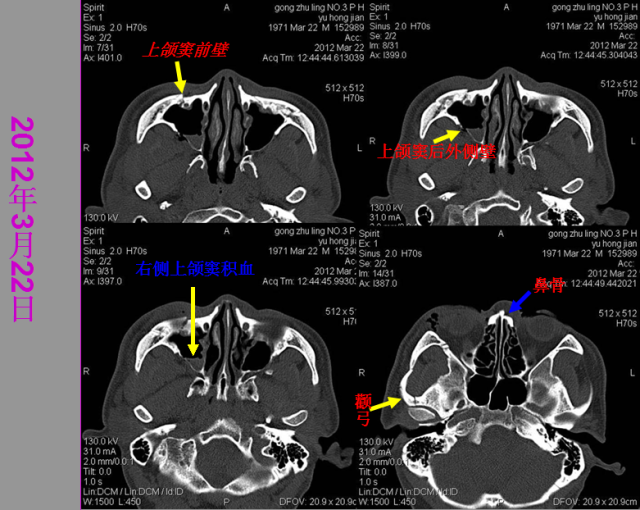

骨折篇

定义:骨折{Fracture}是指骨的完整性和连续性的折裂或粉碎。包括创伤性骨折、疲劳性骨折和病例理性骨折。 临床上以创伤性骨折*常见。